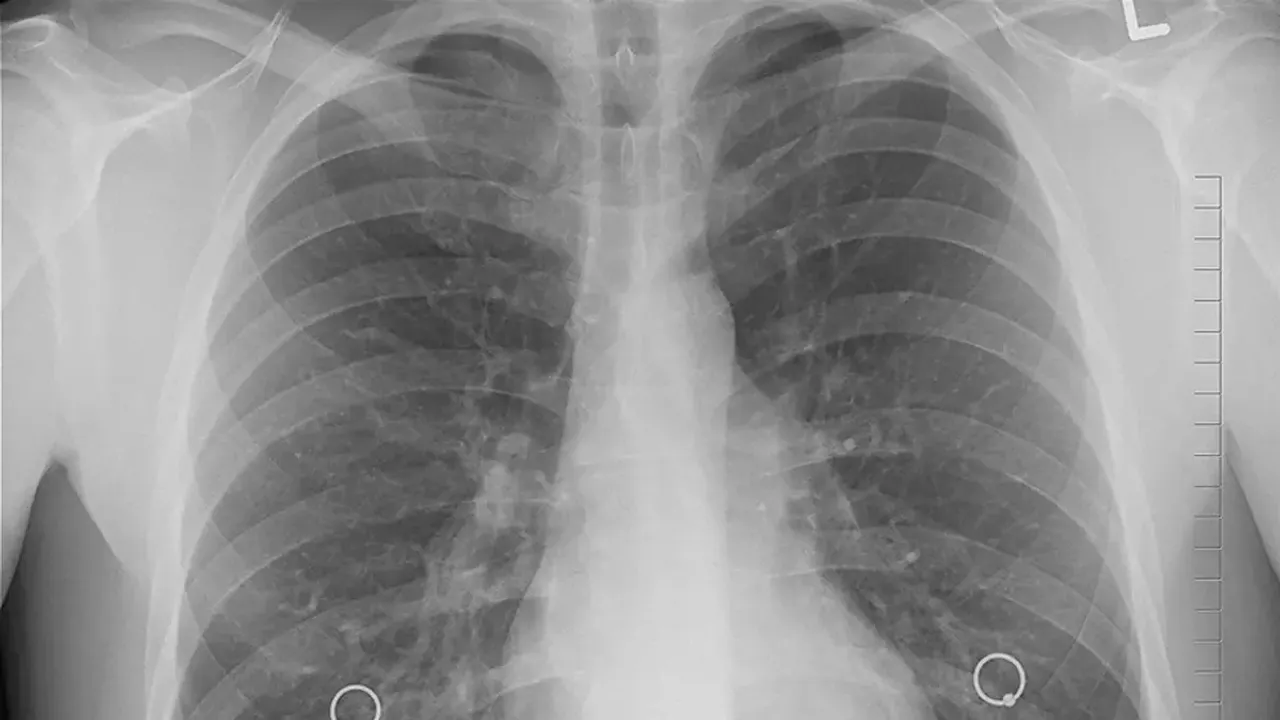

Akciğer kanseri teşhisinin geç aşamalarda konulması, hastalığın tedavi edilebilirliğini önemli ölçüde azaltıyor. Northwestern Medicine'de yürütülen yeni bir çalışma, bu sorunun kökeninde mevcut tarama kılavuzlarının yetersizliğinin yattığını gösteriyor. Araştırma sonuçlarına göre, akciğer kanseri hastalarının yaklaşık üçte ikisi, resmi tarama önerilerine uymadıkları için erken teşhis fırsatından yoksun kalıyor.

Goodwin'in durumu, akciğer kanserinin erken aşamada bulunmasının ne kadar kritik olduğunu göstermektedir. American Lung Association'a göre, akciğer kanseri daha erken bir aşamada teşhis edildiğinde iyileştirilebilme şansı önemli ölçüde artmaktadır. Ancak Goodwin gibi sigara içmemiş genç kadınlar, mevcut tarama kılavuzlarına göre uygun olmadıkları için bu erken teşhis imkanından yoksun kalmaktadırlar.

American Cancer Society'nin verilerine göre, akciğer kanseri Amerika Birleşik Devletleri'ndeki en ölümcül kanser türüdür. Hastalık, her yıl binlerce insanın hayatını almakta ve sağlık sistemi üzerinde muazzam bir yük oluşturmaktadır. Ancak son on yılda, sigara içimdeki azalmalar nedeniyle ölüm oranlarında önemli ölçüde düşüş kaydedilmiştir.